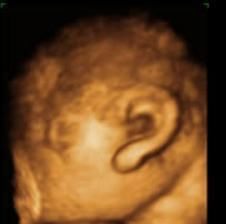

阿薇做四维彩超时,医生看到机器里的画面后,吓得花容失色,她震惊道:

“这位女士,我建议你终止妊娠。通过影像中的分析,你极有可能怀了海豹胎。”

“海豹胎”就是一种四肢残缺或手脚畸形发育的婴儿,因为海豹的手脚短小,故因此得名。